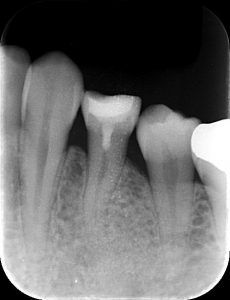

こちらのようにむし歯が大きく

むし歯を取ると歯髄が露出してしまっているようなケースにおいて

MTAとよばれるセメントを埋めます

幸い症状もなく、半年後には新たな組織の形成も認められましたので

歯髄を保存したうえで、治療を完了することができました。